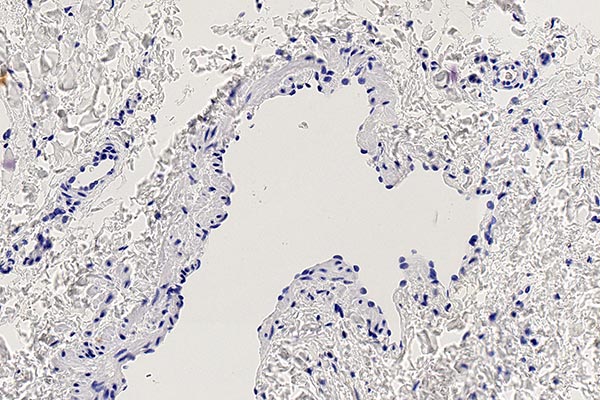

Histopathologischer Schnitt des gewonnenen Biopsiepräparates; Hämatoxylin-Eosin-Färbung, Übersichtsvergrößerung, 20-fach; gut sichtbar die unregelmäßige Wandstruktur der dysplastischen Gefäßräume, typisch für eine Gefäßmalformation. Wieder ist der eigentliche dysplastische Gefäßraum größer als das gewonnene Gewebestück. Daher ist die Gefäßwand auch nicht tubular dargestellt, sondern das Gefäß wie „umgestülpt“ und die Wand außen randbildend ohne ein eigentlich sichtbares rohrförmiges Gefäß. Das mit dargestellte Fettgewebe ist unspezifisch.

Hämatoxylin-Eosin-Färbung, 40-fache Vergrößerung als Übersicht; hier ein anderer Gefäßabschnitt dargestellt. Die unregelmäßige, zum Teil ganz fehlende Wandstruktur der dysplastischen Gefäßräume in der ganzen Läsion ist wiederum typisch für eine Gefäßmalformation.

Hämatoxylin-Eosin-Färbung, 100-fache Vergrößerung; eben sichtbar in dieser Vergrößerung ist die Endothelzellschicht, die die innere Auskleidung eines größeren, dysplastischen Gefäßraumes bildet. Damit stellen sich in dem kleinen Präparatausschnitt die eigentlich im Gefäß innen wandbildenden Gefäßendothelzellen als „außenliegend“ dar, da nicht das gesamte Gefäßareal dargestellt ist. Der Verlauf und die Dicke sowie die Verteilung der darunterliegenden, dunkelrosa gefärbten, glattmuskulären Gefäßwand sind sehr unregelmäßig (Malformation).

Die histopathologische Aufarbeitung zeigte dann auch den typischen Befund einer benignen Gefäßläsion (CD31-positiv) mit dysplastischem, asymmetrisch unregelmäßigem Wandaufbau. Wie für solche Slow-flow-Gefäßmalformationen typisch, ist die glattmuskuläre Gefäßwand nicht überall gleich dick und symmetrisch ausgebildet, sondern fehlt zum Teil sogar ganz (SMA, EvG). Kaum Proliferation des beteiligten Gewebes (Ki67 sehr niedrig). Die fehlende WT1-Positivität der betroffenen Gefäßendothelien ist ein weiterer Hinweis auf eine Gefäßmalformation. Wesentlichstes histopathologisches Unterscheidungsmerkmal zwischen einer lymphatischen Malformation und einer venösen Malformation ist die immunhistochemische Anfärbung des Podoplanin der Gefäßendothelien der Läsion mittels des Antikörpers D2-40. Nur die Gefäßendothelzellen einer lymphatischen Malformation (D2-40 positiv) färben hier an. In dem Präparat zeigten sich zusätzlich auch multiple dysplastische Gefäßmalformationsareale, deren Gefäßendothel nicht mit D2-40 anfärbte, also handelte es sich hierbei um Anteile einer venösen Malformation. Die korrekte histopathologische Diagnose ist daher auch eine kombinierte venolymphatische Malformation. Die klinisch und in der Bildgebung klar im Vordergrund stehende lymphatische Komponente steht in dem Präparat der hier gewonnenen Stanzbiopsie aus der Läsion gegenüber der venösen Komponente eher im Hintergrund.